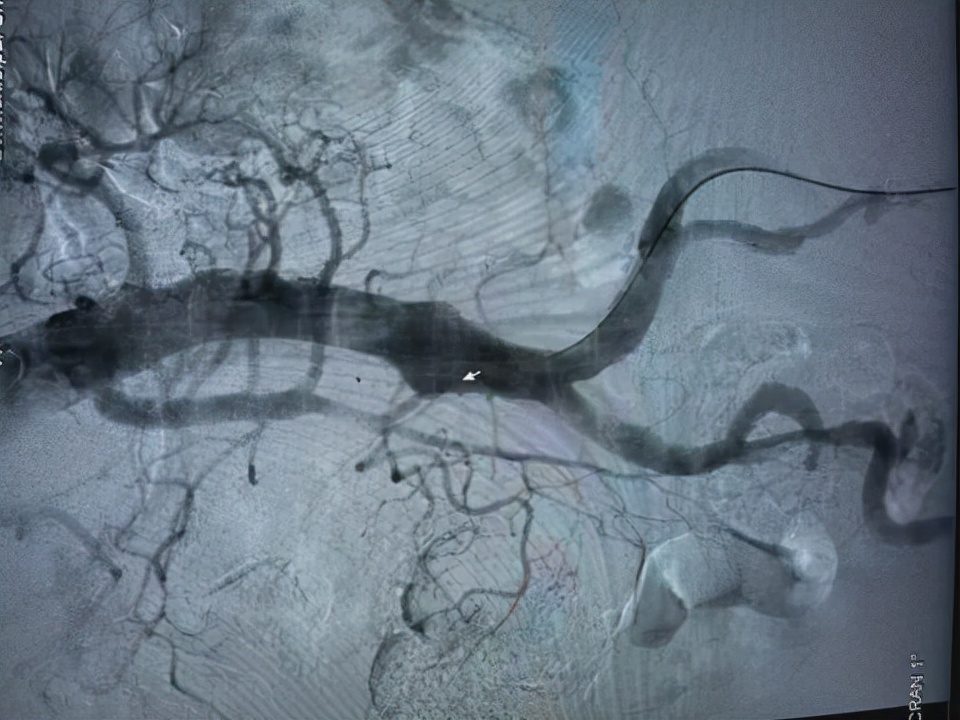

杨永久主任团队迅速对患者进行了 经皮胸主动脉腹覆膜支架腔内隔绝术 。术中通过造影见腹主动脉远端瘤样扩张,直径约3.0cm;左锁骨下动脉远侧主动脉夹层动脉瘤,血管破口距离锁骨下动脉1.5cm。从左侧股动脉穿刺依次置入血管缝合器、血管鞘、和胸主动脉带膜支架后,精确定位后释放支架以封闭动脉夹层破口,避免血管撕裂的进一步扩大。

而介入手术治疗,主要针对DeBakey Ⅲ型。即使用主动脉覆膜支架植入封闭动脉撕裂口,夹层假腔逐渐形成血栓、血管机化,纤维化而使假腔愈合,消除主动脉进一步撕裂而出现破裂风险。随着多个国内外品牌主动脉覆膜内支架上市,使得很多夹层病变复杂的患者能够得到微创,高效的治疗。

(胸主动脉夹层动脉瘤术后:裂口被支架封闭,假腔闭塞,最终疤痕化)